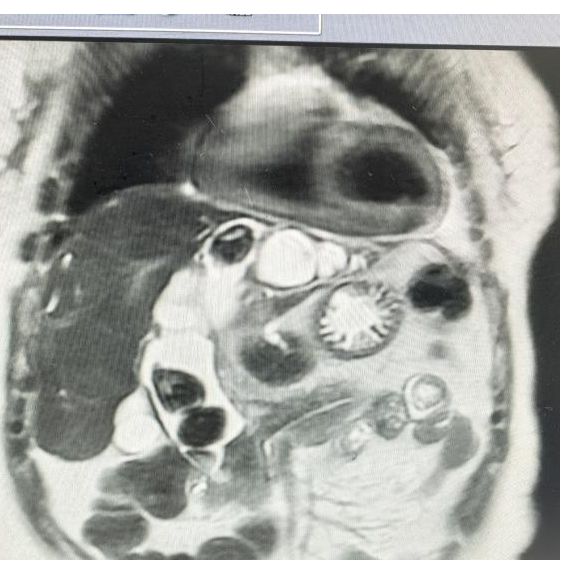

术后复查CT

术后带气管导管送入医院重症医学科(ICU病房)接受精心治疗,密切观察生命体征平稳后再转回肝胆外科病房继续治疗。

让人欣慰的是,奉老太恢复得比预想快得多。科室全面推行的ERAS加速康复方案起了作用:术后尽早下床、尽早进食、优化镇痛,让患者少遭罪、早出院。